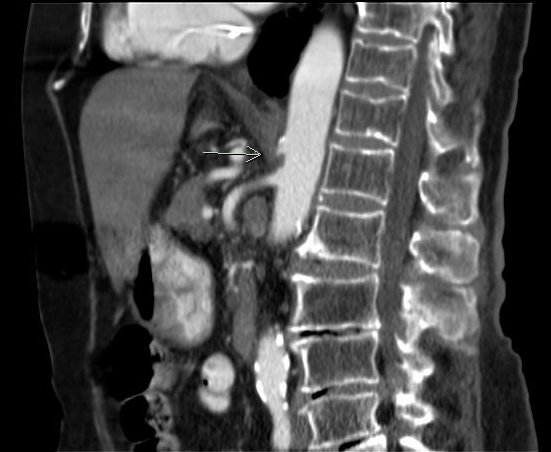

• Celiac Artery compression by the median arcuate ligament

• Post-stenotic dilatation of celiac artery

• Compression will worsen with expiration and improve with inspiration

• CTA is best imaging protocol

• Look for “hook” / “J” sign